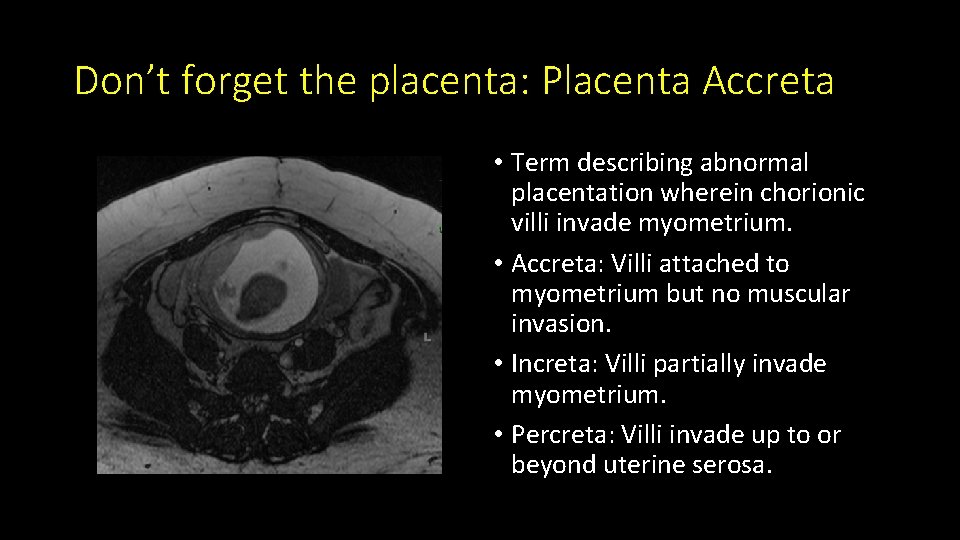

Don’t forget the placenta: Placenta Accreta • Term describing abnormal placentation wherein chorionic villi invade myometrium. • Accreta: Villi attached to myometrium but no muscular invasion. • Increta: Villi partially invade myometrium. • Percreta: Villi invade up to or beyond uterine serosa.